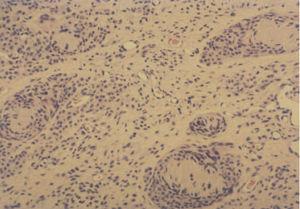

Fig. 3.—Porción profunda del nevo donde se aprecian estructuras con diferenciación neuroide que recuerdan a los corpúsculos de Meissner. (Hematoxilina-eosina, ×100.)

Se extirparon las lesiones tumorales, mostrando todas ellas las mismas características histológicas. Se podían observar los rasgos habituales de un nevo melanocítico congénito gigante, consistentes en islotes de células névicas con actividad juntural en la dermis superficial y estructuras con diferenciación neuroide en la dermis profunda, que recordaban a los corpúsculos táctiles de Meissner. Sin embargo, el hallazgo histológico que más llamaba la atención era la existencia de grandes cantidades de tejido cartilaginoso maduro en la dermis (figs. 2 y 3). En ningún momento se encontró tejido inmaduro o de aspecto atípico.